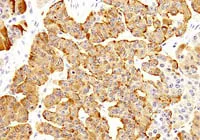

クロモグラニンA

Image

04_img02.jpg